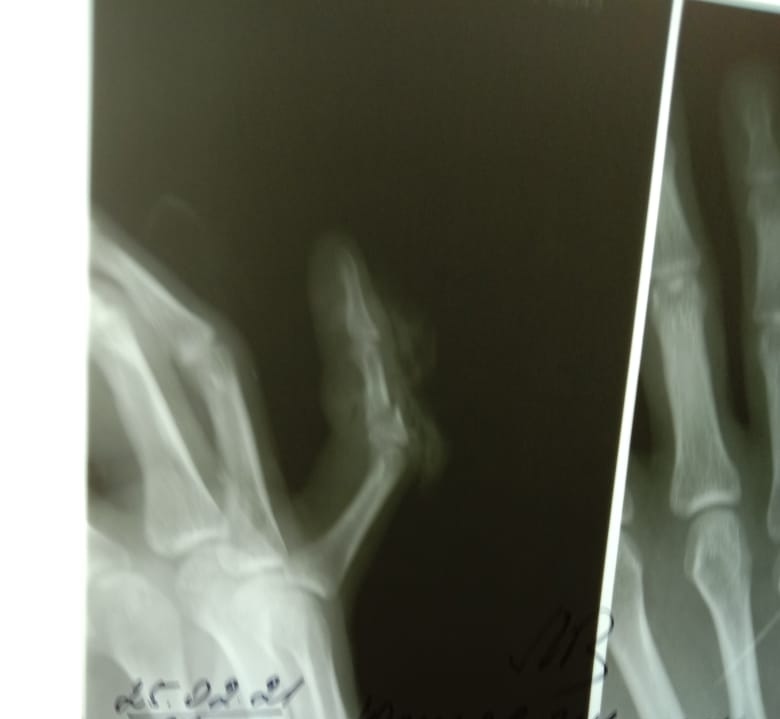

Вот такая же история, мизинец на правой руке тоже. Ну опух, ну болит чуток. Опухоль не спадала, жена заставила сходить в больницу. Сложный перелом в трех местах. Потом операция, хирург матерился, я сознание 2 раза терял. Сверлили кости насквозь, потом 2 спицы туда вставляли, гипс и тд. Но это еще не все. Совпало снимать спицы на новый год нужно было. Ну праздники переждал конечно, потом врач заболел, короче спицы вросли в кость. А когда вырывали спицы я чуть не нагадил под себя!!! Говорили моторика не восстановится, а уж про пианино забудь дружок. Короче все зажило, и на пианино играю, 2 шрама и ноет на погоду!!! 15 лет прошло. Берегите себя.